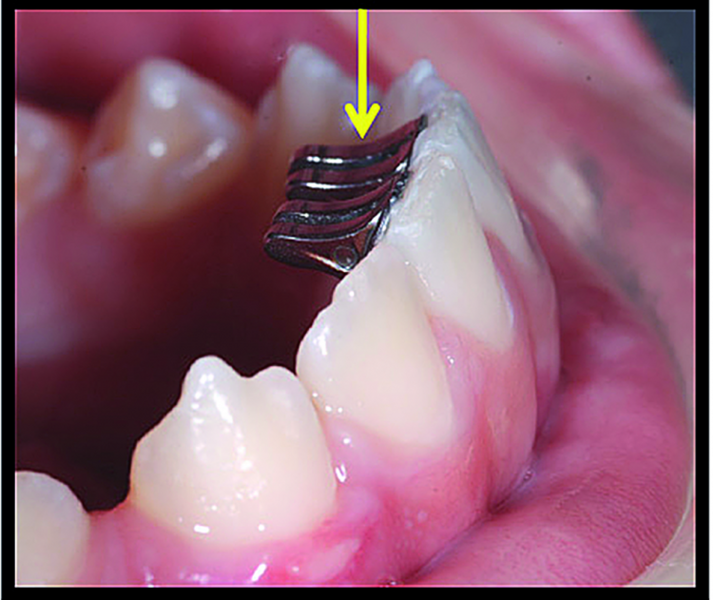

BiTurbo2 system for rapid deep overbite correction